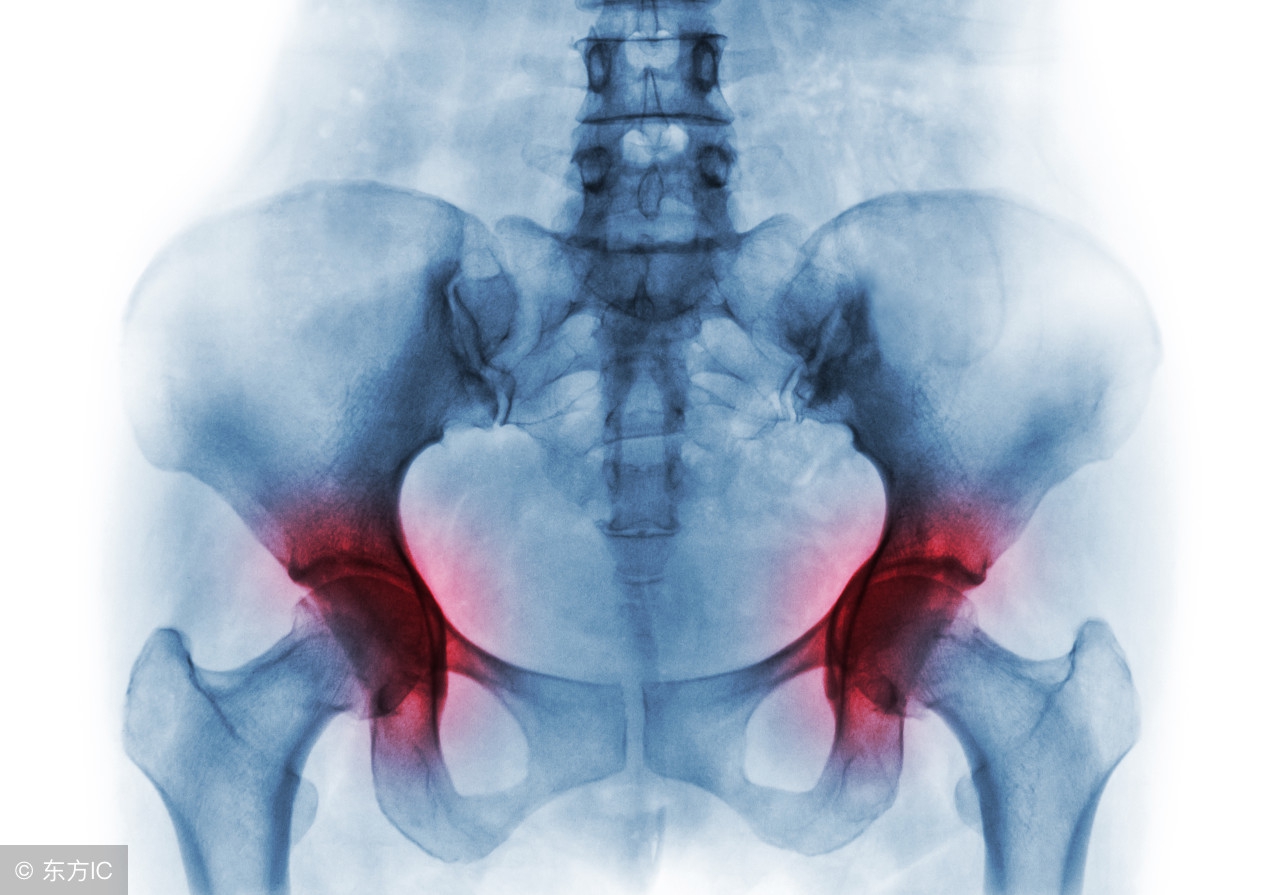

股骨头坏死可以发生在任何年龄段,无性别差异,但有其偏好四十左右酗酒的男士。股骨头坏死开始多表现为髋关节或其周围关节的隐痛、钝痛,蹲起困难,分腿行走不便,活动后加重,进一步发展可导致髋关节的功能障碍,严重影响患者的生活质量和劳动能力,若治疗不及时,也可导致终身残疾。

股骨头坏死主要是由于股骨头血液循环障碍所导致,李建仲教授认为该病早发现、早治疗是关键,在治疗过程中,以“加大循环流量,加强循环动力,加速血液速度”为根本,推拿可以起到松解粘连、促进血运、改善功能、减轻疼痛、疏通经络、调整阴阳等的作用。